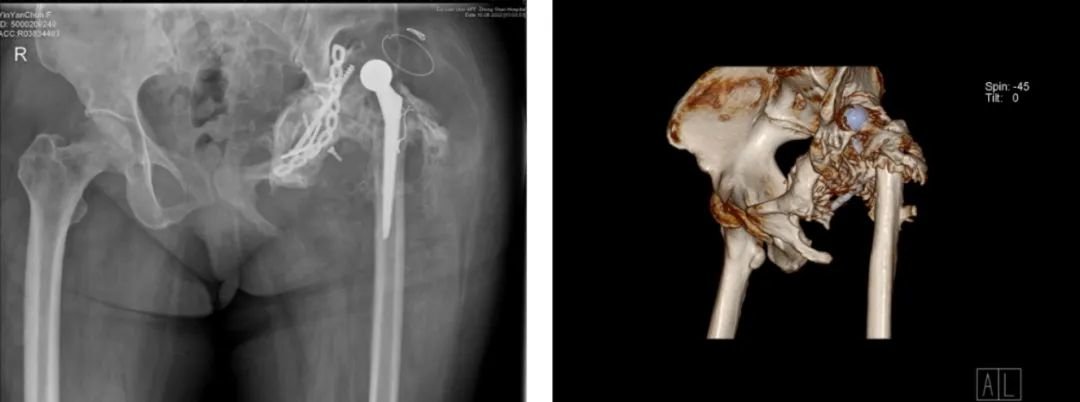

△本次就诊时X线与CT

赵德伟教授团队在仔细讨论病情并认真分析患者髋臼情况后,尹女士的关节可能是由于感染导致,决定按照尹女士的CT数据为其量身定制一款臼杯。从结构上既能通过填充骨缺损恢复股骨头旋转中心的位置,又能提供髂骨和耻骨桥接固定的一体化臼杯。在功能上还能利用3D打印的多孔结构搭载含抗生素,用于术后长期有效的发挥抗炎作用。假体是由伟坦(大连)生物有限公司与北京力达康有限公司共同设计制作。

赵德伟院长及其团队在手术中将松动的臼杯、骨水泥和内植入物取出,对尹女士左髋关节进行了彻底的清创,在多孔结构涂敷含有敏感抗生素的可降解骨水泥之后,精准地安装定制化髋臼假体。尹女士左髋关节的翻修重建手术顺利完成。目前,尹女士术后恢复良好,拟于近日出院,期待她回归正常生活,健康幸福。

△术后X线片